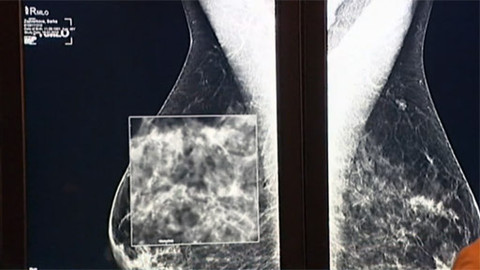

Srdeční frekvence

V desátém vydání magazínu TEP 24 je na místě si říct, co to vlastně tep je a ukázat si, jak vzniká i jak ho lze načas nahradit. S pojmy jako TEP ? ale taky puls, srdeční frekvence či krevní tlak to není tak úplně jednoduché. Každopádně dnes anesteziologové či kardiologové zachytí díky nejmodernějším metodám bezpočet detailů, které jim v případě zástavy srdce umožňují záchranu života a co nejmenší následky pro pacienta.